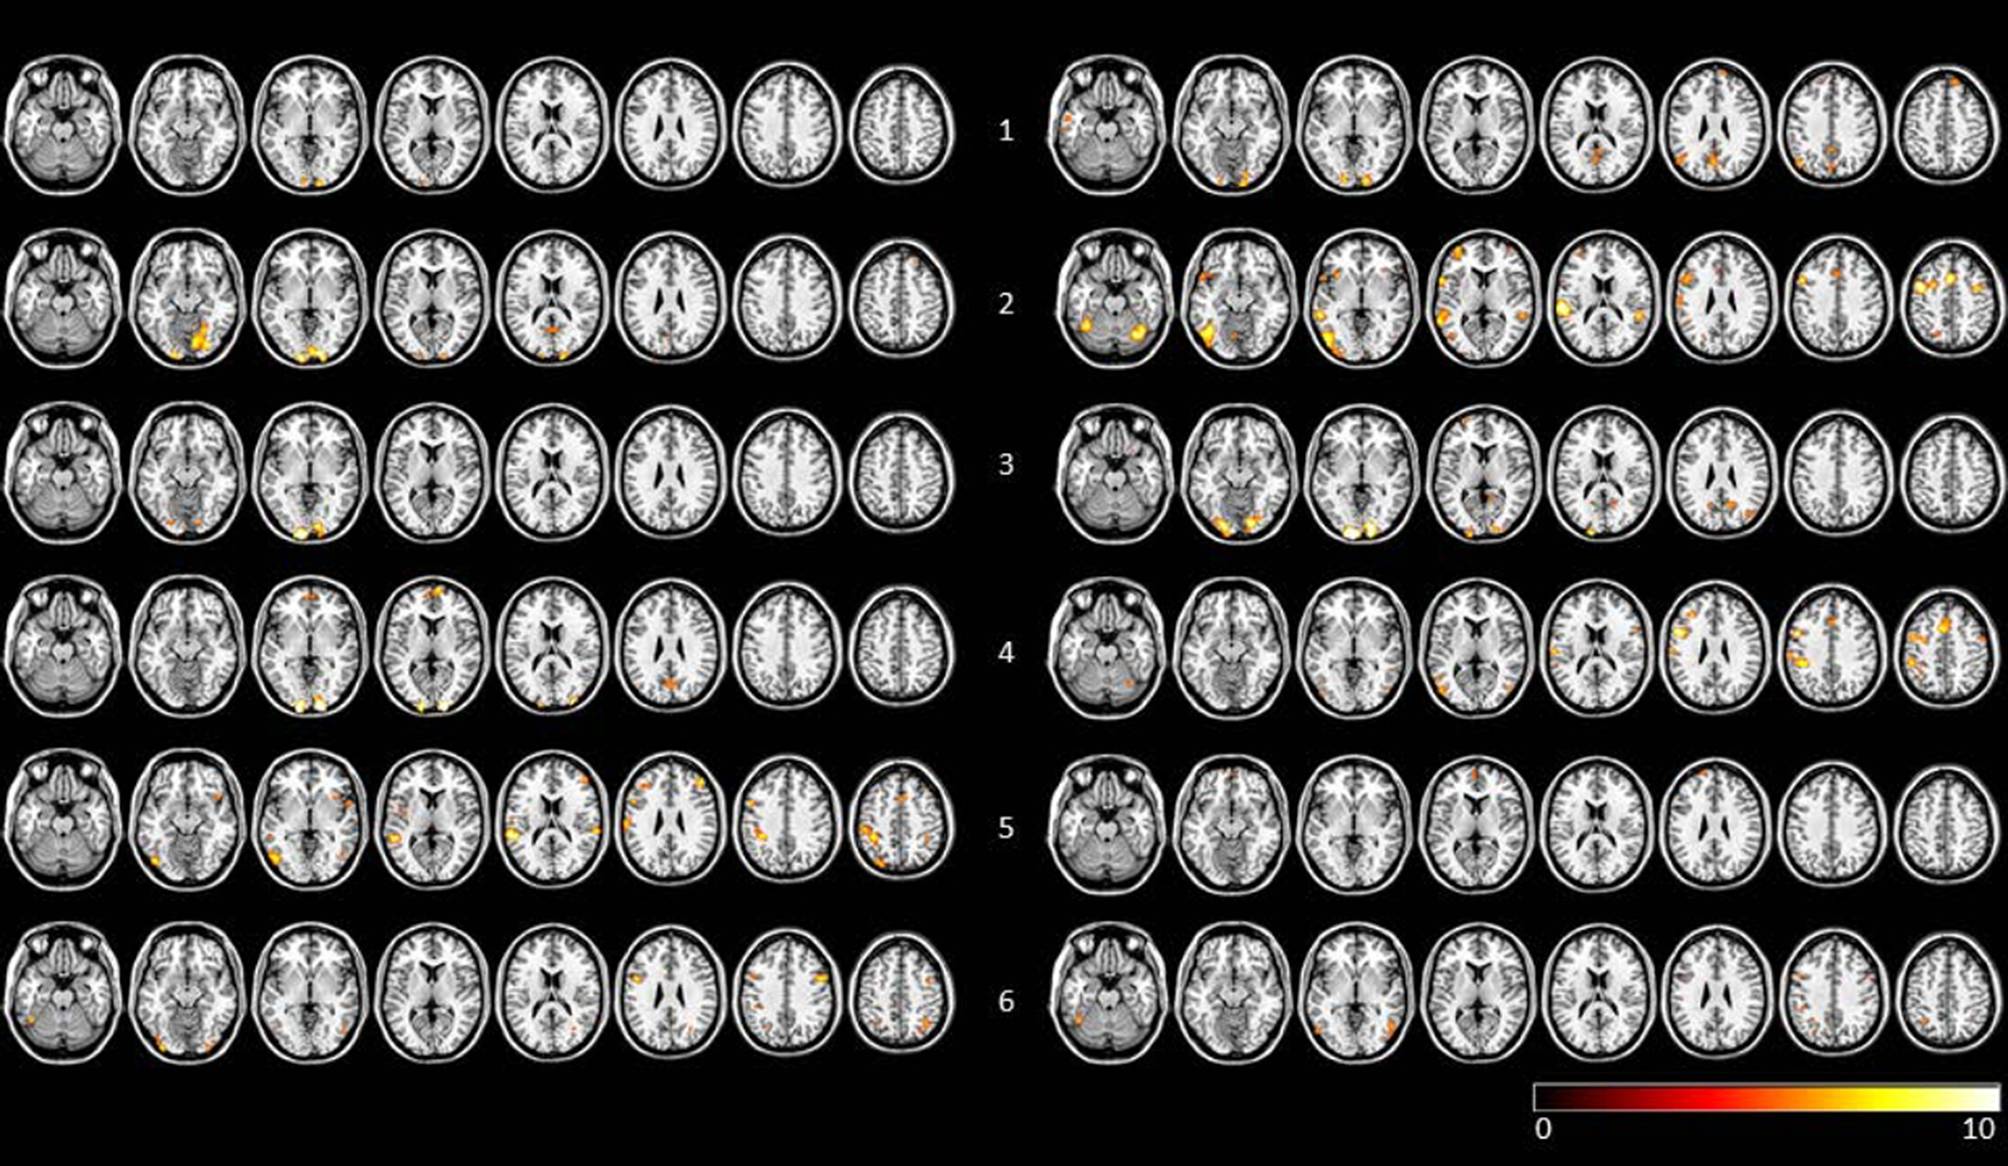

In 4 of the 6 AP + CR subjects the number of clusters increased, whereas in 4 out of the 5 AP subjects the number of clusters decreased (mean number of clusters: AP + CR = 5.53, SD 12.79, AP = −5.8, SD 6.9; see Table 1 for details). Individual activation maps for AP + CR subjects before and after therapy are shown in Fig. 1 and for AP subjects in Fig. 2.

Fig. 2

Visualization of FFX results of pre and post therapy n-back task runs for AP subjects (FWE corrected, p < 0.005). Row labelling refers to subject number. To the left of the subject number individual scans before therapy are shown, to the right of the subject number the scans after therapy are shown. Data are visualized on a standard template using MRIcron. AP group subjects with atypical antipsychotics, FFX fixed effects analysis, FWE family-wise error